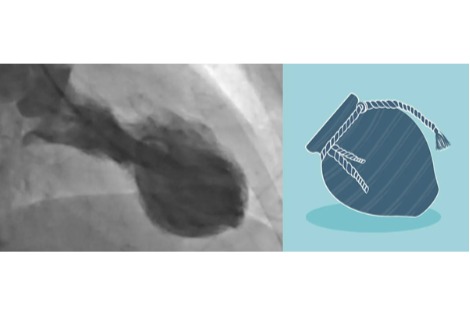

تُعد الخلايا العصبية الجسيمية إيجابية MOR1 ذات أهمية كبيرة جزئيًا لأن لها روابط مباشرة مع نفس الخلايا العصبية المنتجة للدوبامين والتي يُعتقد أنها تتدهور في مرض باركنسون. في حين يتميز مرض باركنسون بفقدان الدوبامين وفقدان الحركة ، يتميز مرض هنتنغتون بارتفاع وانخفاض مستوى الدوبامين والحركات المفرطة. في الواقع ، الأدوية الوحيدة التي تمت الموافقة عليها من قِبل إدارة الأغذية والعقاقير (FDA) لعلاج داء هنتنغتون هي الأدوية التي تقلل من إفراز الدوبامين ، وبالتالي تعمل على تثبيط الحركات غير الطبيعية. لكن هذه العلاجات تأتي مع آثار جانبية خطيرة محتملة ، مثل الاكتئاب والانتحار.

قد يوفر هذا الاكتشاف الأخير أدلة آلية لتقلبات الدوبامين في مرض هنتنغتون ويوفر سبلًا لعلاجات أكثر تحديدًا.